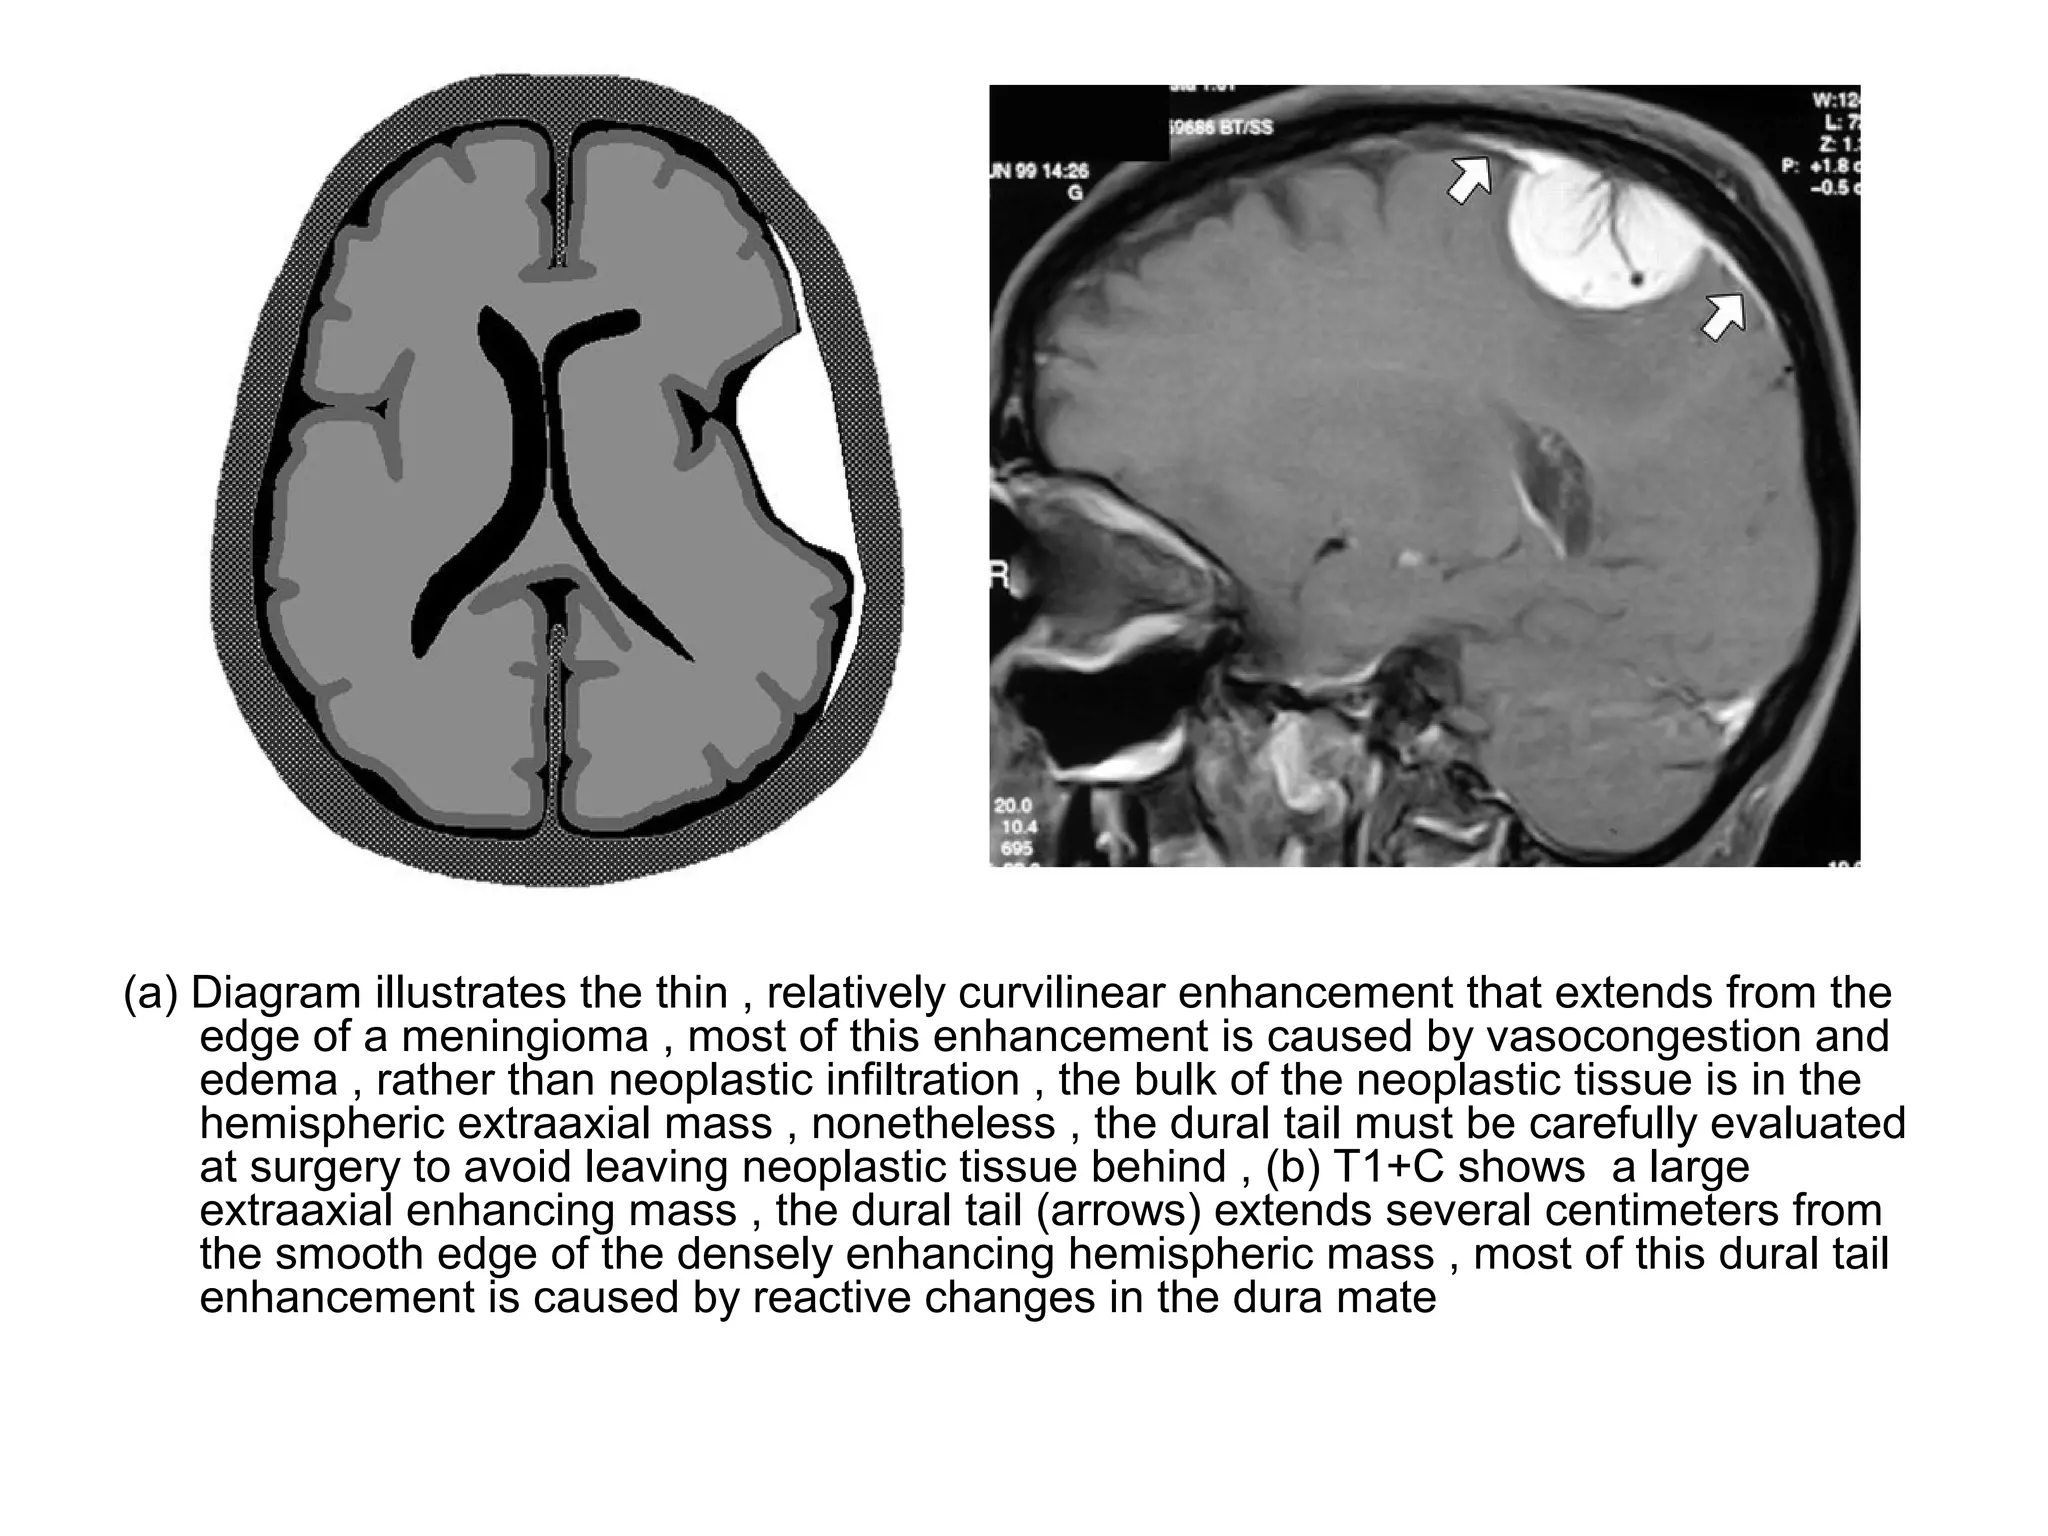

(a) Diagram illustrates the thin , relatively curvilinear enhancement that extends from the

edge of a meningioma , most of this enhancement is caused by vasocongestion and

edema , rather than neoplastic infiltration , the bulk of the neoplastic tissue is in the

hemispheric extraaxial mass , nonetheless , the dural tail must be carefully evaluated

at surgery to avoid leaving neoplastic tissue behind , (b) T1+C shows a large

extraaxial enhancing mass , the dural tail (arrows) extends several centimeters from

the smooth edge of the densely enhancing hemispheric mass , most of this dural tail

enhancement is caused by reactive changes in the dura mate